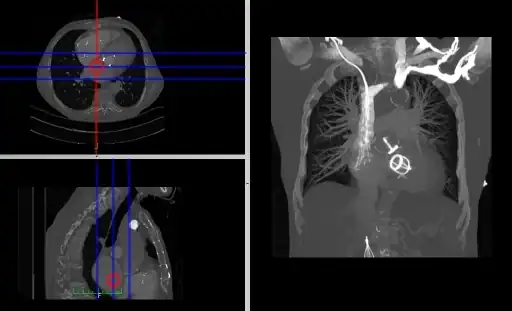

- Composite MPR Display

- Coronal and sagittal reconstructions are referred to as Orthogonal MPRs because the perspectives generated are from planes of image data which are at right angles to each other. Composite MPR displays can be generated so that linked cursors or crosshairs can be used to locate a point of interest from all three perspectives, as illustrated in Figure 5.19.

- Oblique MPRs are possible by defining angled planes through the voxel data , as illustrated in Figure 5.20.

- Here the plane can be defined in, say, the axial images (red line, top left) and a maximum intensity projection (the limits used are highlighted by the blue lines), for example, can be displayed for the reconstructed plane (right). This technique is useful when attempting to generate perspectives in cases where the visualization of three-dimensional structures is complicated by overlapping anatomical detail.

- A final variant on the MPR theme is the generation of a three-dimensional display showing all three orthogonal projections combined so that a defined point of interest locates the intersection of the planes, as illustrated in Figure 5.22.

- The point of intersection is located for illustrative purposes at the centre of the voxel data in the figure. It can typically be placed at any point in the 3D data using interactive controls. In addition, the perspective used for the rotating sequence can be manipulated interactively to improve the visualization of a region of interest. Note that the image sequence illustrated is one from a myriad of perspectives that can thus be generated. Note also that slice projections (e.g. MIPs) can be combined with this form of display to provide additional perspectives on a feature of interest.